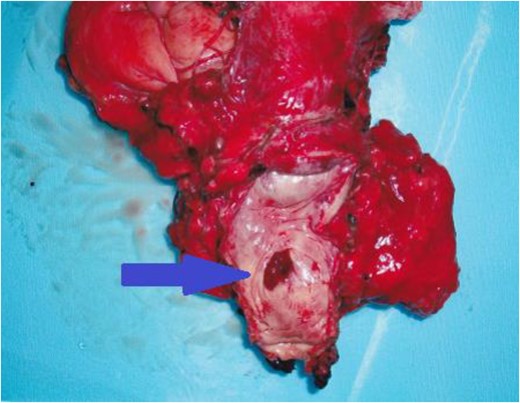

On admission, we performed standard open total cystectomy with lymph node excision and ileal conduit. The resected specimen showed the mass on the anterior vaginal wall (Fig. 2). Histopathological examination of the specimen showed adenocarcinoma tumor that continues to anterior vaginal wall, but urethral diverticular wall could not be identified (Fig. 3). We could not establish a diagnosis of urethral diverticulum; however, we clinically diagnosed as urethral diverticular adenocarcinoma. The proximal margin was negative, and all lymph nodes were negative. Because the post-surgical course was uneventful, the patient was discharged from our hospital on Day 27 post-surgery. The patient is doing well without recurrence or metastasis for 12 months.

The resected specimen showed the mass on the anterior vaginal wall.